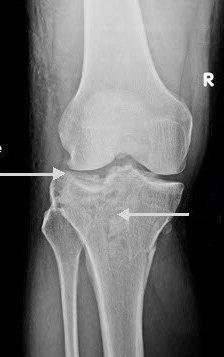

This film shows a lateral tibial plateau fracture with depression and comminution.

There is a less obvious extension of the fracture through the medial tibial plateau and in fact the knee is no longer connected to the shin!